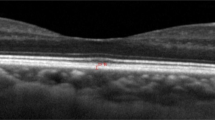

OCT examination was performed by an experienced technician using a spectral-domain OCT (3D OCT-1, Topcon, Tokyo, Japan). Topcon 3D OCT-1 is a non-contact SD-OCT system that performs a fully automated “alignment, focus, and capture” procedure by capturing 50,000 axial scans per second [19]. Herein, the “3D wide scan mode” was selected to provide a 12 mm × 9 mm scan measurement and topographical maps of the optic nerve and macula (Fig. 1a). The mode also featured an automatic segmentation of RNFL, total retina, GCIPL, and GCC (Fig. 1b–d, e).

The 12 × 9 mm scan region (A). Measurement areas for cpRNFL circle (B). Macula ETDRS grid (C), macula 6 circle for GCIPL, and GCC (D) overlaid with example projected images. Full retinal thickness (distance between the red and green boundaries); ganglion cell + inner plexiform layers (distance between the yellow and blue boundaries); ganglion cell complex (distance between the red and blue boundaries, vitreal to inner nuclear layer) (E). All the images were set with the right eye orientation.

The macula full retinal thickness (FRT) was defined as the distance between the inner limiting membrane (ILM) and the outer segments/retinal pigment epithelium junction boundary. It was divided into nine quadrants based on the ETDRS map (Fig. 1c). The diameters of the three circles on the ETDRS map are 1, 3, and 6 mm. In the same line, GCIPL thickness was defined as the distance from the interface between the NFL and ganglion cell layer (GCL) to the interface between the inner plexiform layer (IPL) and inner nuclear layer (INL). GCC was defined as the distance between the internal limiting membrane and the interface between the IPL and INL. It was the sum of RNFL and GCIPL (Fig. 1e). The temporal-superior-nasal-inferior-temporal (TSNIT) circle with a diameter of 3.4 mm was placed automatically at the optic disc center to obtain the optic nerve head parameters. The thickness of cpRNFL was assessed over 4 quadrants and 12 clock-hour sectors around the TSNIT circle (Fig. 1b). The optic disc contour was automatically detected. However, the disc area, cup area, rim area, cup/disc (C/D) vertical diameter, C/D area, cup volume, and rim volume were measured.

Thickness and distributions of macular FRT, GCIPL, and GCC

Supplementary Table 1 shows the thickness and distribution data of macular FRT, GCIPL, and GCC. The average thickness of macular FRT, GCIPL, and GCC was 279.19 ± 10.61 μm, 76.41 ± 4.70 μm, and 108.15 ± 6.15 μm, respectively (Fig. 2a). The superior region (305.64 ± 12.07 μm) of the inner circle of macular FRT was the thickest area. It was followed by the inferior, nasal, and temporal regions, respectively, without any significant differences across regions. Nonetheless, the outer ring of the nasal region (295.36 ± 13.17 μm) was significantly thicker than the temporal (P < 0.01), superior (P < 0.01), and inferior (P < 0.01) regions (data not shown in tables).

A Thickness distribution maps of macular layers. Topographic distributions of macular FRT, GCIPL, and GCC thickness in different sectors are shown through the picture. B 12 clock-wised sections of cpRNFL thickness distribution. The mean ± SD values (lm) are presented. S superior, I inferior, N nasal, T temporal.